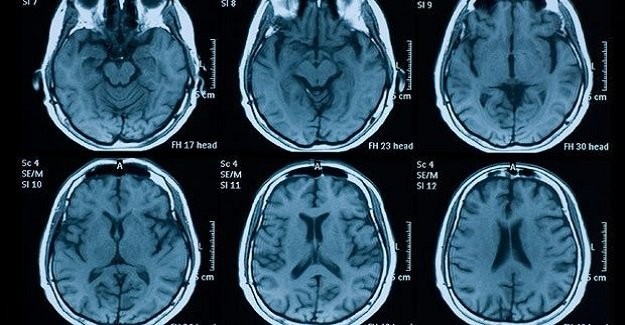

Şok eden haber uzmanlar tarafından açıklandı. 18 yaşındaki genç kız cinsiyet değiştirme ameliyatı ile erkek oldu. Çekilen MR'ı tüm bilim dünyasını şok etti.

Viyana Üniversitesi bilim insanları erkeklik hormonu verdikleri genç kızın beyin MR'ını çekti. Bilim insanları genç kızın, cinsiyet değiştirdikten ve hormon verildikten sonra birden fazla işi aynı anda yapamadığını ve bu kabiliyetlerinin köreldiğini söyledi.

Uzmanlar yaptıkları tetkiklerden sonra beyinde dil ve bölgeler arası iletişimi sağlayan alanın zayıfladığı anladılar. Bu durum yıllardır süren 'cinsiyet değiştirmek doğru mu?' sorularına tekrar gündeme taşıdı.

18 yaşındaki transeksüel gence 4 hafta boyunca testosteron hormonu verildi. Bunun sonrasında uzmanlar dil kontrolünü de sağlayan Broca ve Wenicke adındaki iki alanda gri maddenin azaldığını fark etti.

Profesör Rupert Lanzenberger yaşanan bu olayla ilgili, "Testosteron hormonuna maruz kalan ve kalmayan beyin arasında ciddi bir fark görüyoruz. Bunu transeksüel bir bireyi incelemeden anlamamız imkansızdı. Bu sonuçlar cinsiyet hormonlarının önemini anlatıyor." şeklinde konuştu.